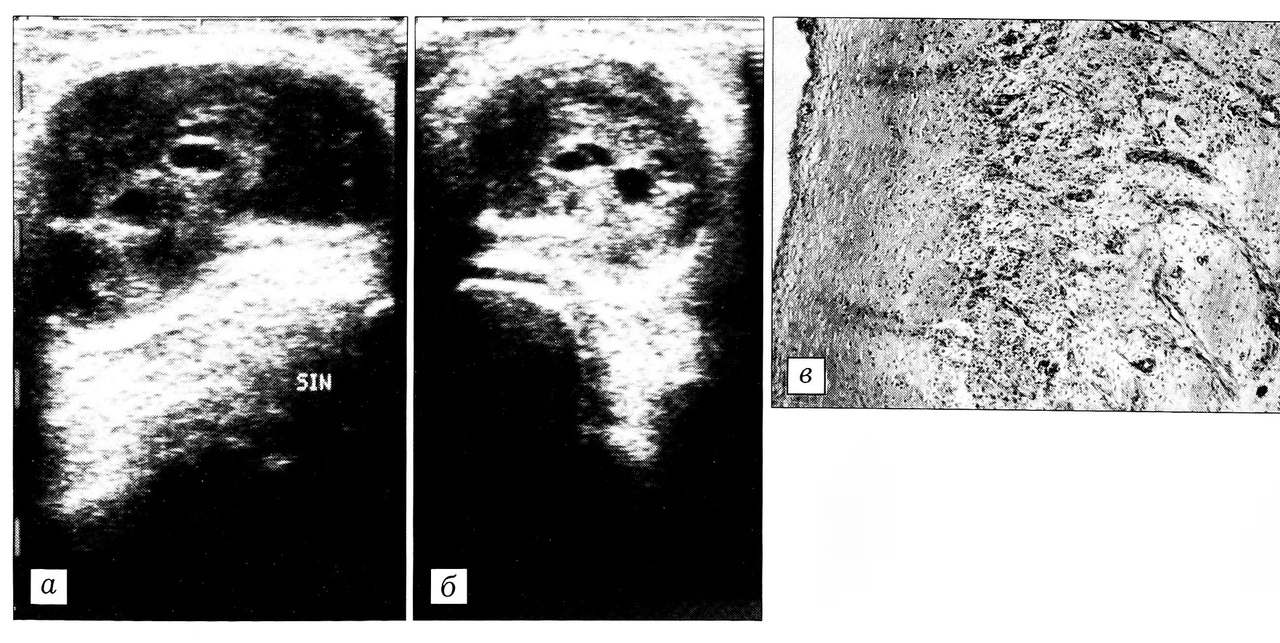

Вторую группу составили 12 больных с рентгенологически подтвержденной II стадией гонартроза при давности кисты 12,1±4,17 мес (р < 0,05). На артросонограммах у них визуализировалось эхонегативное образование с четкими контурами, с утолщенной синовиальной оболочкой повышенной эхогенности, с ворсинами и единичными нежными перегородками. Толщина синовиальной оболочки колебалась от 2,6 до 7,9 мм, составляя в среднем 4,28±0,15 мм. Содержимое кисты неоднородное, с эхоплотными, без акустической тени включениями. Шейка кисты прослеживалась менее четко (рис. 2, а).

Рис. 2. Киста Бейкера, II период организации. а — сонограмма с продольным сканированием: визуализируются утолщение синовиальной оболочки до 7 мм, ворсины и единичные нежные перегородки. Содержимое неоднородное, с эхоплотными, без акустической тени включениями; б, в — гистологическая картина стенки кисты: выраженные пролиферативные изменения во внутреннем слое (б), врастание тяжей клеток в фибринозные массы (в) (окраска гематоксилином и эозином, об. 16, ок. 10).

При гистологическом исследовании в стенке кисты (рис. 2, б) отмечались выраженные пролиферативные изменения, особенно во внутреннем слое, что приводило к его значительному утолщению. При этом тяжи соединительнотканных клеток врастали в фибринозные сгустки, образуя нежные спайки (рис. 2, в). В некоторых случаях выявлялись гипертрофированные ворсины с утолщенным синовиальным слоем. В глубоком слое наблюдались очаговые разрастания грануляционной ткани, в которой преобладали клетки фибробластического ряда, а также обнаруживались макрофагоциты, плазматические клетки и лимфоидные инфильтраты по ходу сосудов.

Итак, выявленные структурные изменения характеризовались выраженным утолщением синовиальной оболочки с наличием ворсин и единичных нежных перегородок. Содержимое кисты становилось неоднородным, появлялись эхоплотные включения. Гистологически определялось значительное утолщение стенки кисты, главным образом за счет внутреннего слоя и формирования тяжей соединительнотканных клеток, организующих фибринозные массы.

Описанные изменения структуры, свидетельствующие об усилении пролиферативных процессов, определяют период прогрессирования структурной организации кисты и носят необратимый характер.